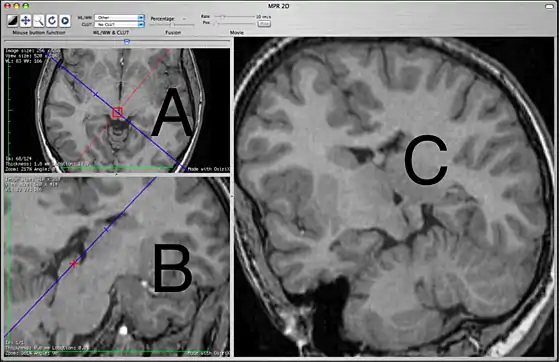

This 2D MPR Viewer allows generating a MPR slice in any position and orientation through the 3D volume. This mode shows three viewing ports. In the picture above, the two on the left are labeled A and B. The third, on the right, is labeled C.

The primary purpose of the A and B view ports is to specify the plane that will be shown in the C view port. The A and B view ports are partially obscured by lines used specify the plane to be seen in C. These lines cannot be hidden. In this sense, the C view port is designed for diagnostic viewing and the other two view ports are primarily to specify what is to be shown in C. The view ports are not all equal, which may be different from what users of other MPR interfaces are expecting. View port A shows a blue line which corresponds to the orientation of what is being seen in C and also contains a red line that corresponds to what is seen in B. View port B shows only a blue line that also corresponds to what is seen in C. View port C has no lines.

The specifying view port A will show the original images in the plane that they were originally acquired, most commonly the axial plane. You can scroll through these images to choose the one that you want to work off. The specifying view port B shows planes that are orthogonal to view port A. If A is showing an axial image then on initially opening the 2D MPR Viewer, B will show a sagittal image. The specific orthogonal plane that is being created in B is indicated in the A view port as a red line. Under these initial circumstances, C will be showing a coronal reconstruction that corresponds to the blue line.